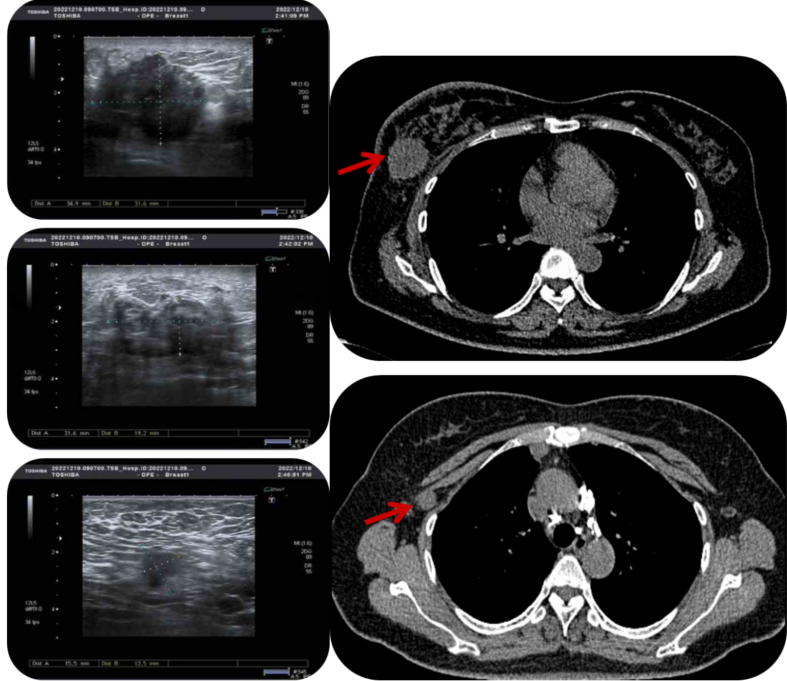

影像学检查

乳腺彩超(2022.12.10):右乳可见两个低回声团块,大小分别为34.9mm×31.6mm和31.6mm×19.2mm,BI-RADS 5类,伴右腋下淋巴结肿大。

PET/CT(2023.01.04):提示右乳多发高代谢癌灶,并广泛转移至右侧腋窝、纵膈、肺门等多处淋巴结,同时伴有双肺及右侧胸膜转移。